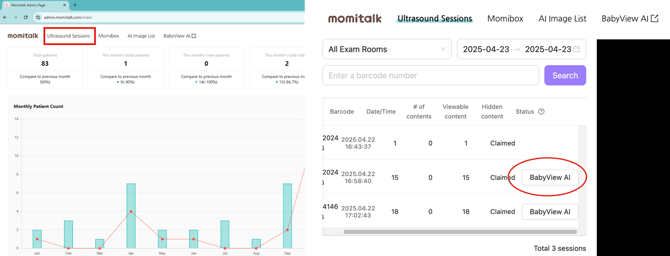

[Step 1] Open the Session

- Go to admin.bomee.io → [Ultrasound Sessions]

- Search by barcode or date.

- Click BabyView AI next to the desired session.

(Button only appears if there is at least one captured image.)